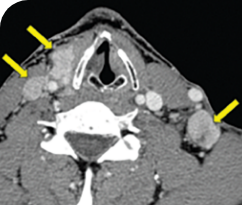

Clinical presentation1

- Patient was assessed to have metastatic, rapidly progressive, RAl-refractory PTC based on imaging that revealed multiple metastatic sites, including the neck, mediastinum, lung, scalp, and bones

- Biopsy of a scalp lesion helped to confirm the PTC metastasis

- Metastases to the brain and liver were observed after progression on systemic treatments

Response in primary and metastatic lesions1

MRIa imagery of the lungs. Arrow indicates large target lesion in left lung.1

SCAN 1: LUNG

MRIa imagery of the brain. Arrow indicates large target lesion in left lung.1

aMRI, magnetic resonance imaging.

Images courtesy of Dr Fabian Pitoia.